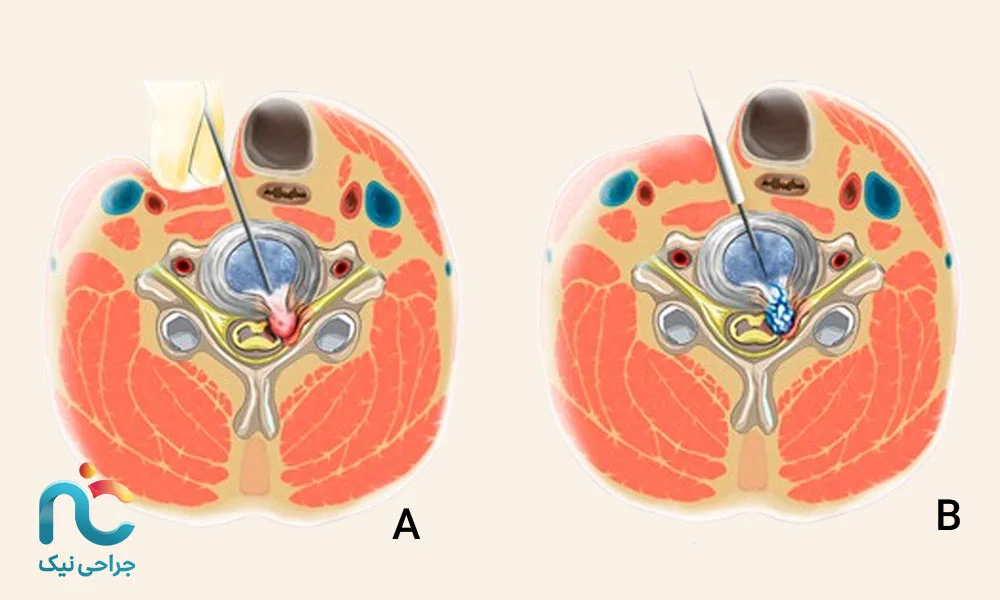

اگر بخواهیم ساده بگوییم، جراحی اندوسکوپیک دیسک گردن یعنی درمان دیسک با کمترین برش ممکن و بدون آسیب به ساختارهای اطراف ستون فقرات. در این روش، به جای باز کردن گردن با برشهای بزرگ، از یک لوله باریک و دوربین مخصوص استفاده میشود که داخل آن منبع نور و ابزارهای جراحی قرار دارند. این دوربین تصویر دقیقی از محل بیرونزدگی دیسک را روی مانیتور نشان میدهد و جراح دیسک گردن میتواند با دقت میلیمتری، قسمت آسیبدیده را خارج کند یا فشار را از روی عصب بردارد.

۱. روش قدامی (Anterior Approach)

در این روش، جراح از جلوی گردن وارد میشود. این مسیر اجازه میدهد بدون دست زدن به عضلات و استخوانهای پشت گردن، مستقیماً به دیسک برسد. معمولاً برای بیرونزدگیهای مرکزی یا مواردی که فشار روی نخاع وجود دارد از این مسیر استفاده میشود. برش بسیار کوچک است و بعد از عمل، جای زخم تقریبا نامشخص میماند.

۲. روش خلفی (Posterior Approach)

در این حالت، جراح از پشت گردن وارد ناحیه آسیبدیده میشود. این مسیر زمانی انتخاب میشود که بیرونزدگی دیسک به سمت عقب یا کنار باشد و فشار روی ریشههای عصبی بیشتر از پشت ایجاد شده باشد. در این روش، عضلات کمی کنار زده میشوند اما با کمک اندوسکوپ آسیبی به آنها وارد نمیشود.

۳. روش ترانسفورامینال (Transforaminal Approach)

این روش جدیدتر و ظریفتر است. در آن، جراح از مسیر بین مهرهها و از کنار وارد میشود؛ جایی که اعصاب از آن عبور میکنند. این تکنیک مخصوص مواردی است که دیسک فقط بخشی از عصب را درگیر کرده و نیاز به دقت بالا دارد. با این روش میتوان بدون جابهجایی زیاد عضلات یا استخوان، فشار را مستقیماً از روی عصب برداشت.